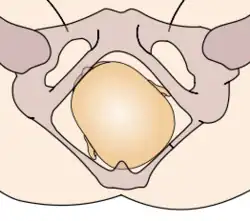

In obstetrics, a cephalic presentation or head presentation or head-first presentation is a situation at childbirth where the fetus is in a longitudinal lie and the head enters the pelvis first; the most common form of cephalic presentation is the vertex presentation, where the occiput is the leading part (the part that first enters the birth canal).[1] All other presentations are abnormal (malpresentations) and are either more difficult to deliver or not deliverable by natural means.

The movement of the fetus to cephalic presentation is called head engagement. It occurs in the third trimester. In head engagement, the fetal head descends into the pelvic cavity so that only a small part (or none) of it can be felt abdominally. The perineum and cervix are further flattened and the head may be felt vaginally.[2] Head engagement is known colloquially as the baby drop, and in natural medicine as the lightening because of the release of pressure on the upper abdomen and renewed ease in breathing. However, it severely reduces bladder capacity resulting in a need to void more frequently.[3]

The vertex is the area of the vault bounded anteriorly by the anterior fontanelle and the coronal suture, posteriorly by the posterior fontanelle and the lambdoid suture and laterally by 2 lines passing through the parietal eminences.

In the vertex presentation, the occiput typically is anterior and thus in an optimal position to negotiate the pelvic curve by extending the head. In an occiput posterior position, labor becomes prolonged, and more operative interventions are deemed necessary.[4] The prevalence of the persistent occiput posterior is given as 4.7%.[4]